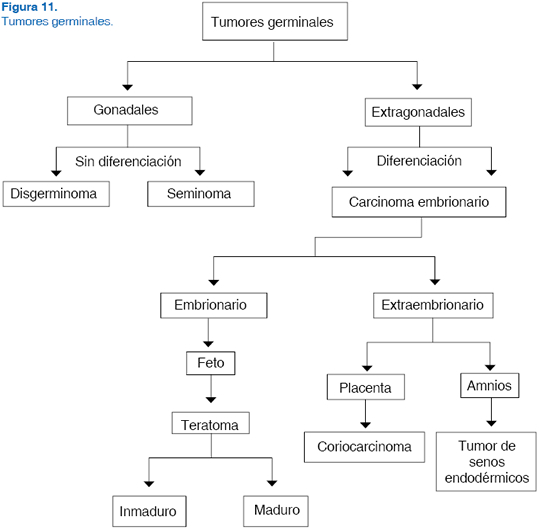

Los tumores germinales son un grupo de neoplasias cuya localización puede ser gonadal o extragonadal y derivan de células germinales primordiales.1,2 Bajo este término se agrupan tanto tumores benignos (quistes epiteliales, teratomas y teratomas inmaduros) como tumores malignos3,4 (disgerminoma, coriocarcinoma, carcinoma embrionario, seminoma, tumor de seno endodérmico) y tumores con histología mixta (Figura 11).14